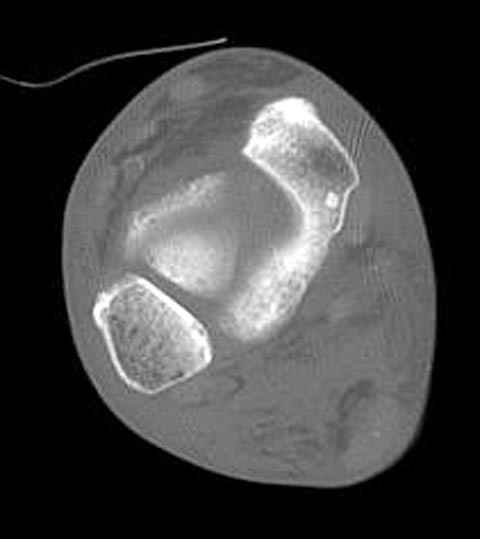

Уважаемые участники русского Ортофорума, поздравляю всех со всеми прошедшими праздниками: Новым годом, Рождеством, Hanukkah, Kwanzaa, желаю участникам всего наилучшего и здоровья.Повреждение таранной кости.Больной 81г автоавария, повреждение таранной кости, здесь снимки. Какие рекомендации?Djoldas Kuldjanov, MDDepartment of Orthopedic SurgerySt. Louis University Medical Center

Вдогонку по поводу перелома таранной кости, больная 81, не страдает диабетом, перелом закрытый, в первый же день поступления ограничились временным наружным фиксатором (как на снимке).

За пару недель насчитал 5 больных с переломом таранной кости, из них двое с двусторонним повреждением.

Из-за отека на стопе тактика лечения у всех была

одинаковая: временная наружная фиксация до спадения отека, при изолированных переломах они выписывались домой и через дней 7 госпитализировались на оперативное лечение.

Примеры на снимке...